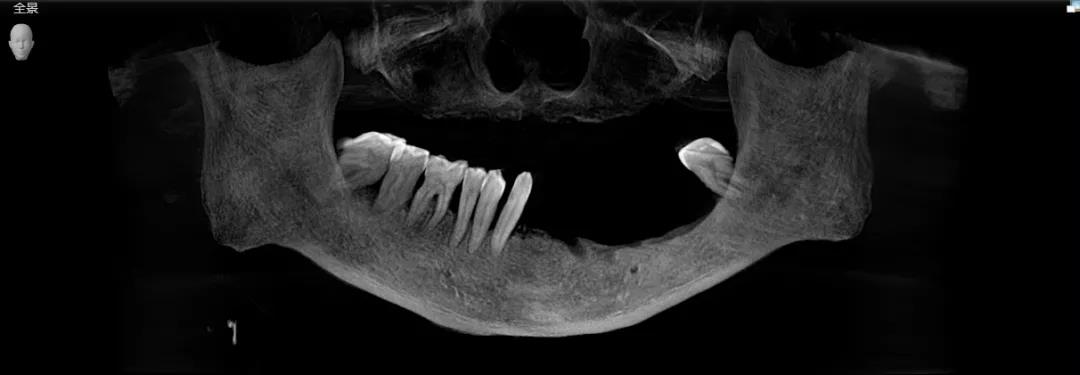

康老第一次来口扫时获取的牙片

通过数字化扫描设备获取的牙片了解到,康老的右侧下颌3号牙出现了松动、2号牙到6号牙之间出现了局部缺失。

为他拔完牙后拍摄的牙片

并且下颌左侧的后牙区骨质疏松,为他规划的种植区距离下槽牙神经很近。

一般人正常的种植区为正梯形,而康老的情况比较特殊,是倒梯形,会导致种植体植入根尖的部分缩短,加大种植难度。